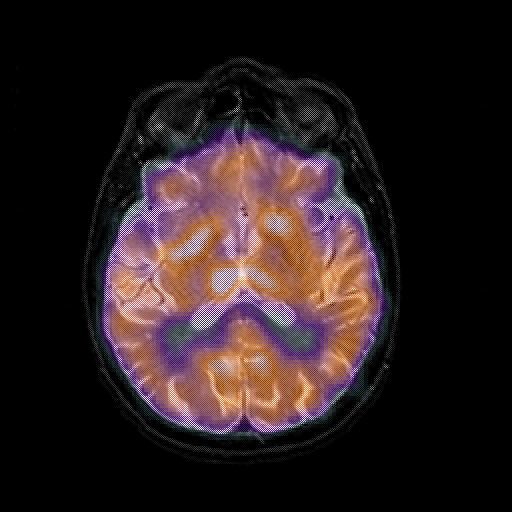

overlay 1: Slice 29

Slice 29